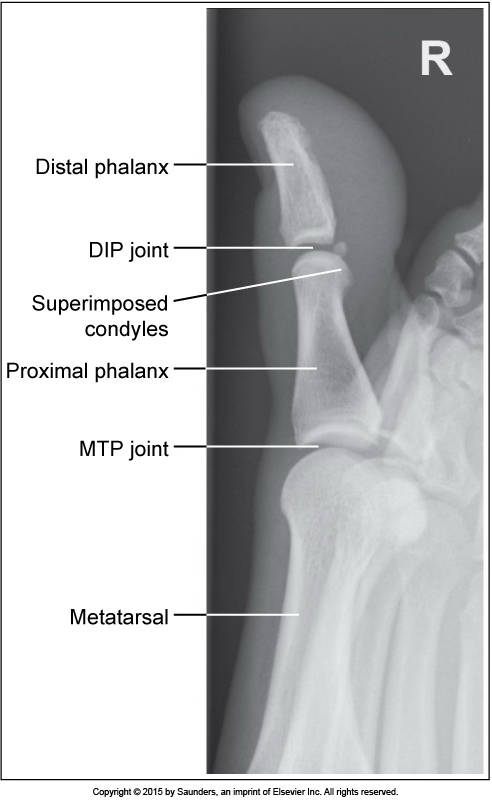

AP oblique toe

excessive toe obliquity

CR not aligned parallel with the IP and MTP jt spaces

lateral toe

accurate positioning